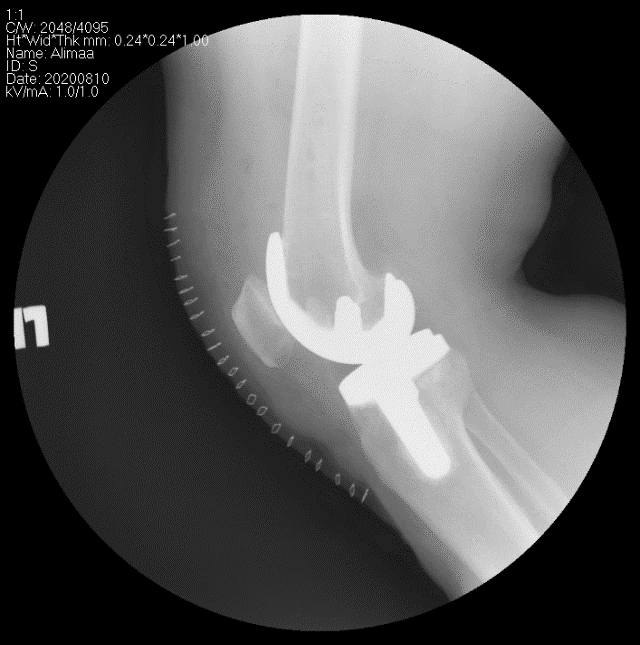

Өвдөгний үе бүтэн солих мэс засал (TKA) image1

Хагалгааны өмнө

Хагалгааны дараах